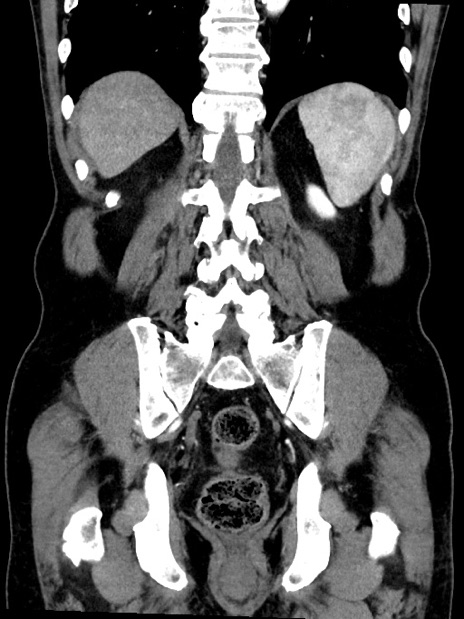

症例35(冠状断像)

【症例】70歳代 男性

【主訴】腹部膨満、嘔吐

【現病歴】昨日より腹部膨満感出現。本日増悪し、仙痛出現。嘔吐あり、受診。

【既往歴】糖尿病、胆摘後

【身体所見】BP 149/80mmHg、HR 74/min、BT 35.9℃、腹部:膨満、軟、圧痛なし。腸雑音減弱あり。上腹部正中切開瘢痕あり。

【データ】WBC 13500、CRP 1.72